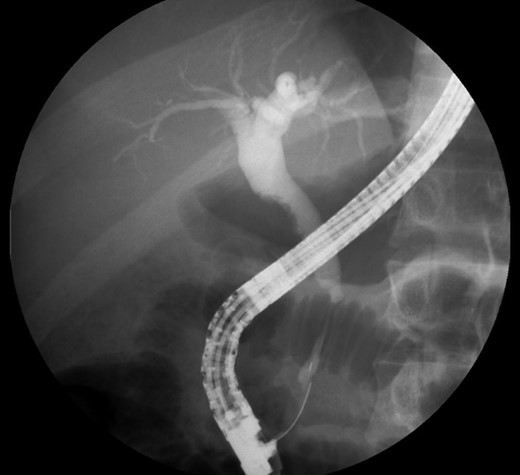

Endoscopic retrograde cholangio-pancreatography (ERCP) showed a lobular pancreas with an enhancing heterogeneous pseudonodular mass located in the pancreatic head. The main pancreatic duct (MPD) appeared a well-defined non-beaded narrowing duct. The common bile duct (CBD) showed no narrowing or strictures until the intrapancreatic portion which presented an irregular stenosis of 2 cm length and dilatation upstream the area of stricture.

ERCP. Heterogeneous pancreatic parenchyma and pseudonodular appearance of the pancreatic head. Wirsung duct with no stenosis or obstructions. Common bile duct with normal caliber until the intrapancreatic portion where a highly suspicious of malignancy 2 cm irregular stenosis is seen.